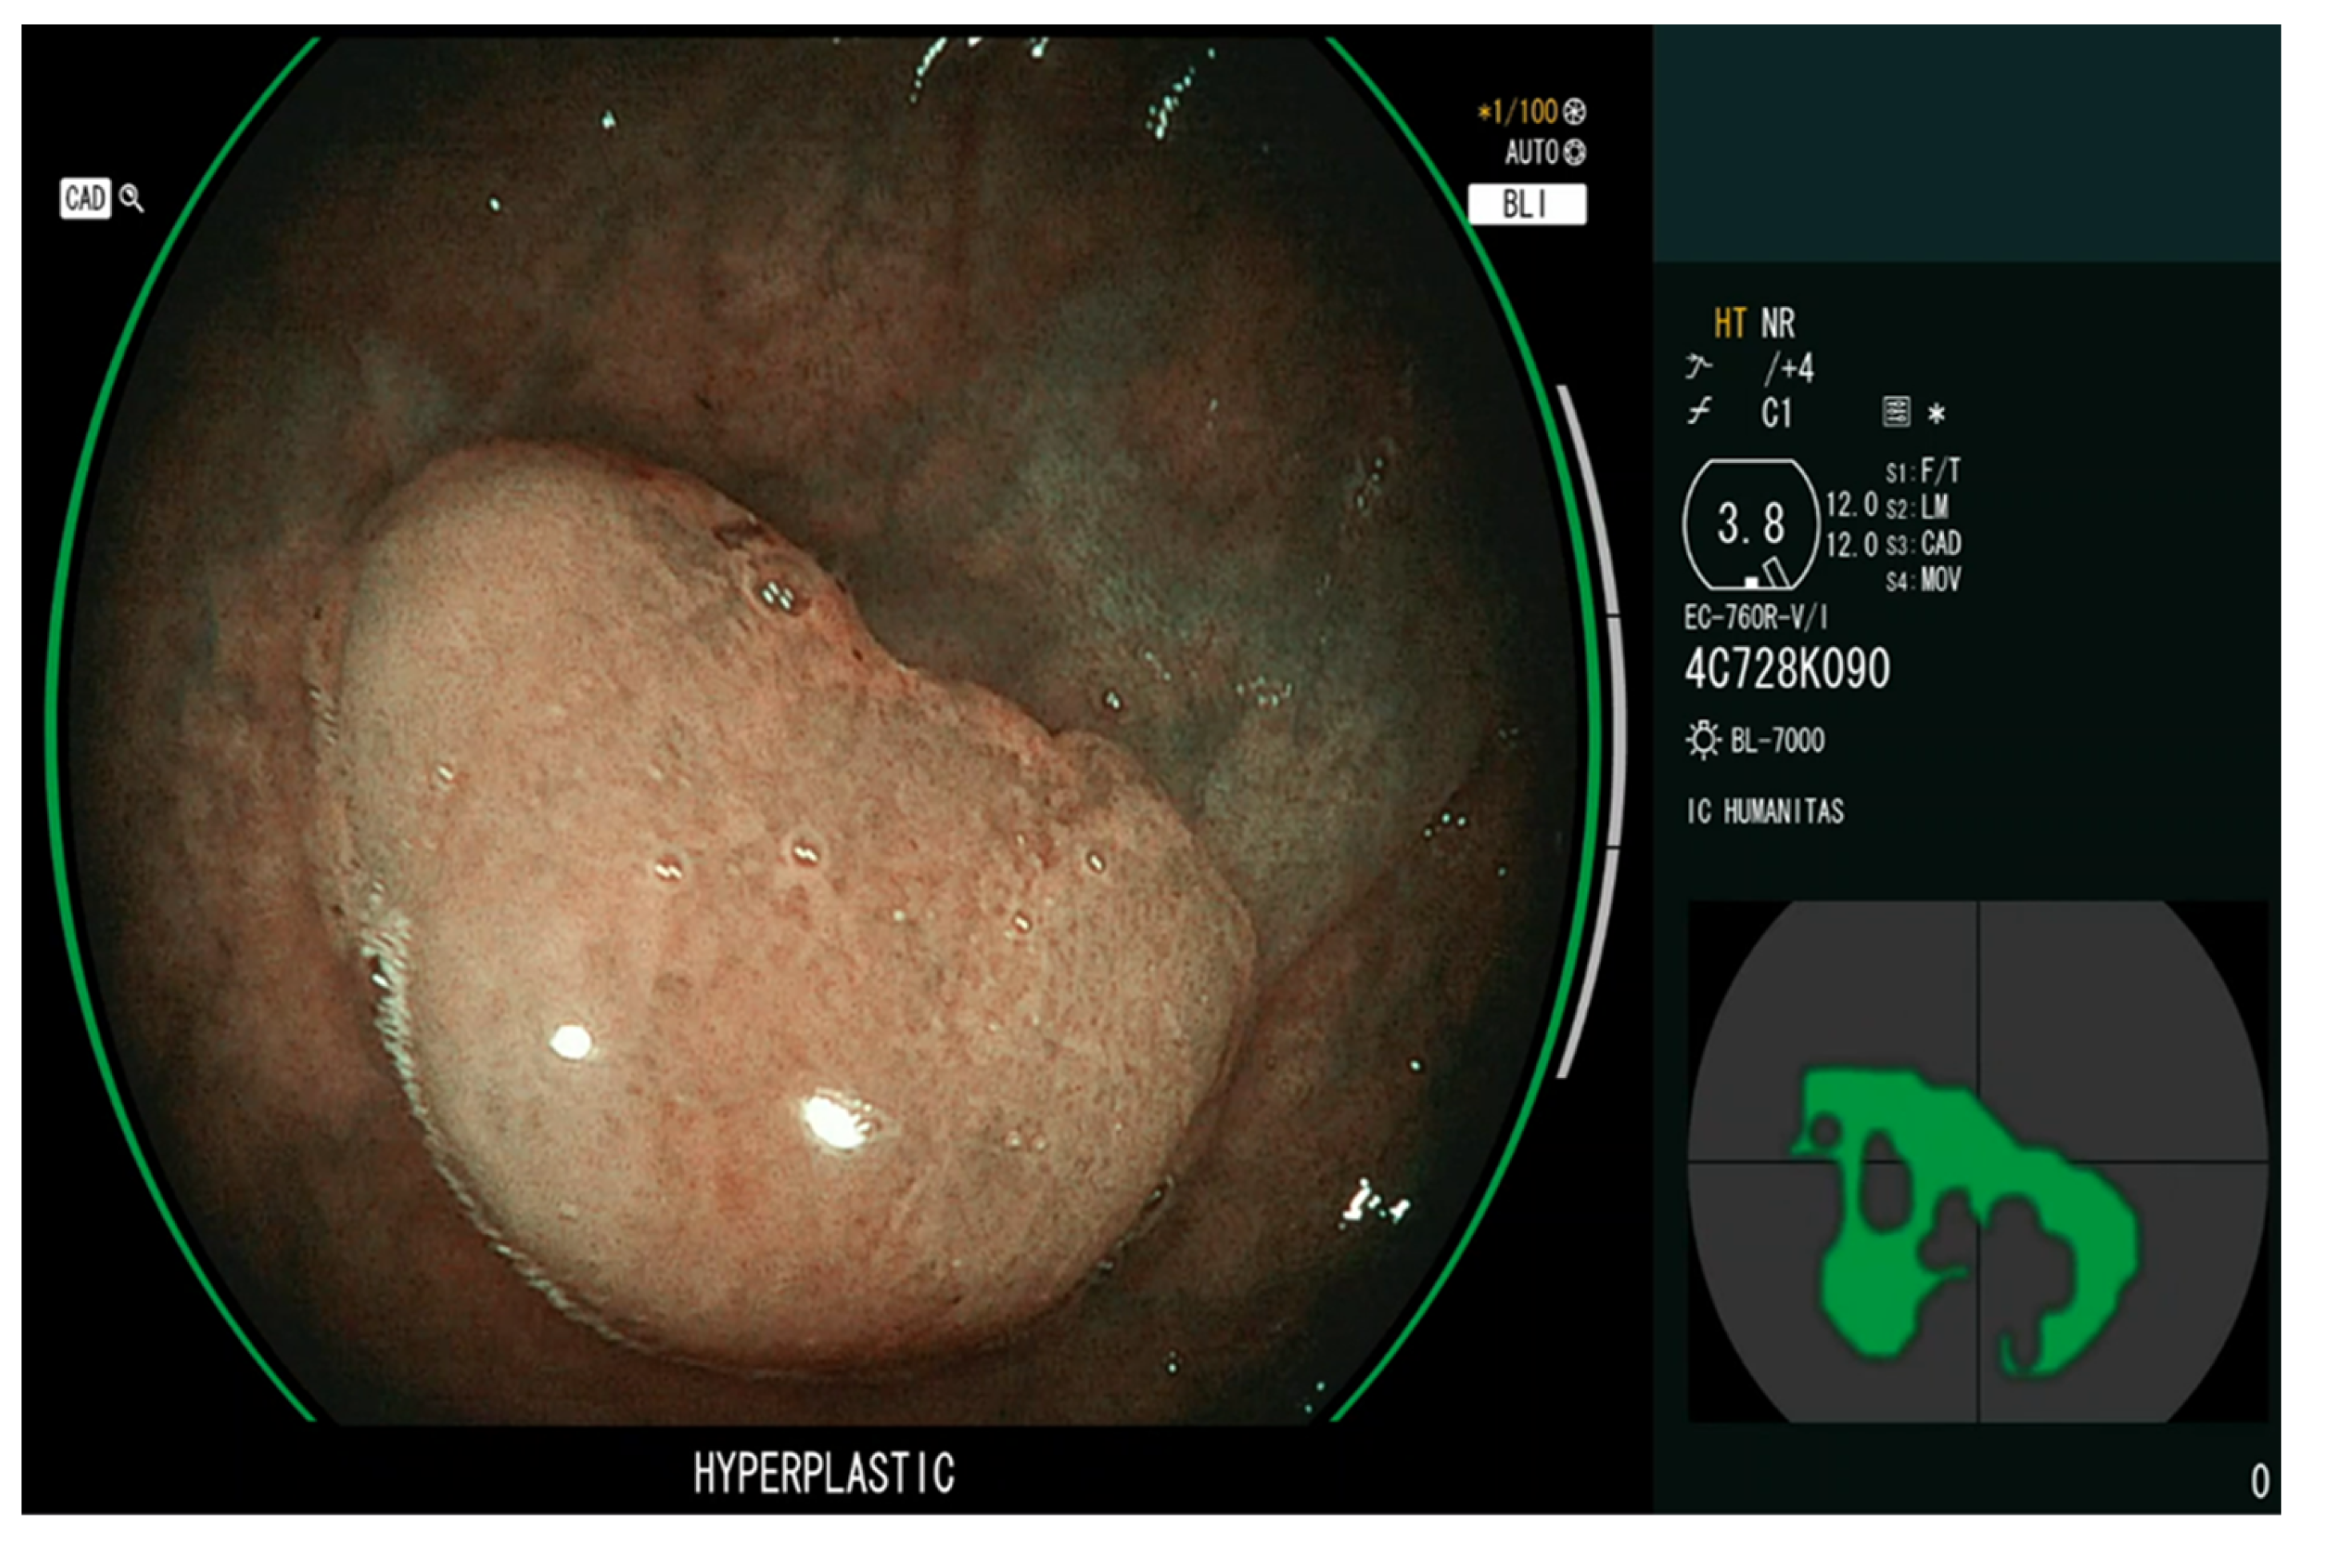

3.2. Artificial Intelligence-Assisted Characterization (CADx)